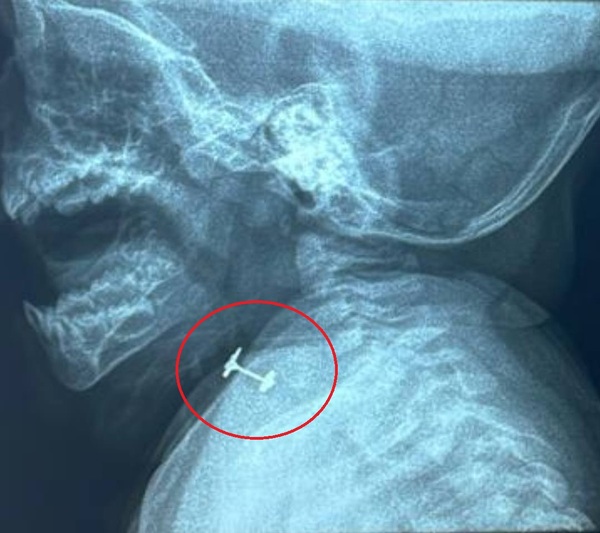

Beba de 10 meses casi muere asfixiada luego de tragar su arito | Unicanal

Médicos del Ineram salvaron a una beba de tan solo 10 meses que llegó con un cuadro de asfixia parcial luego de tragar un arito. ...[Leer más]